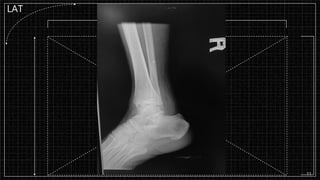

LAT

▪ Film : Rt. Ankle AP, LAT, Mortise

Investigation

▪ Plain Film

▫ AP

▫ LAT

▫ Mortise